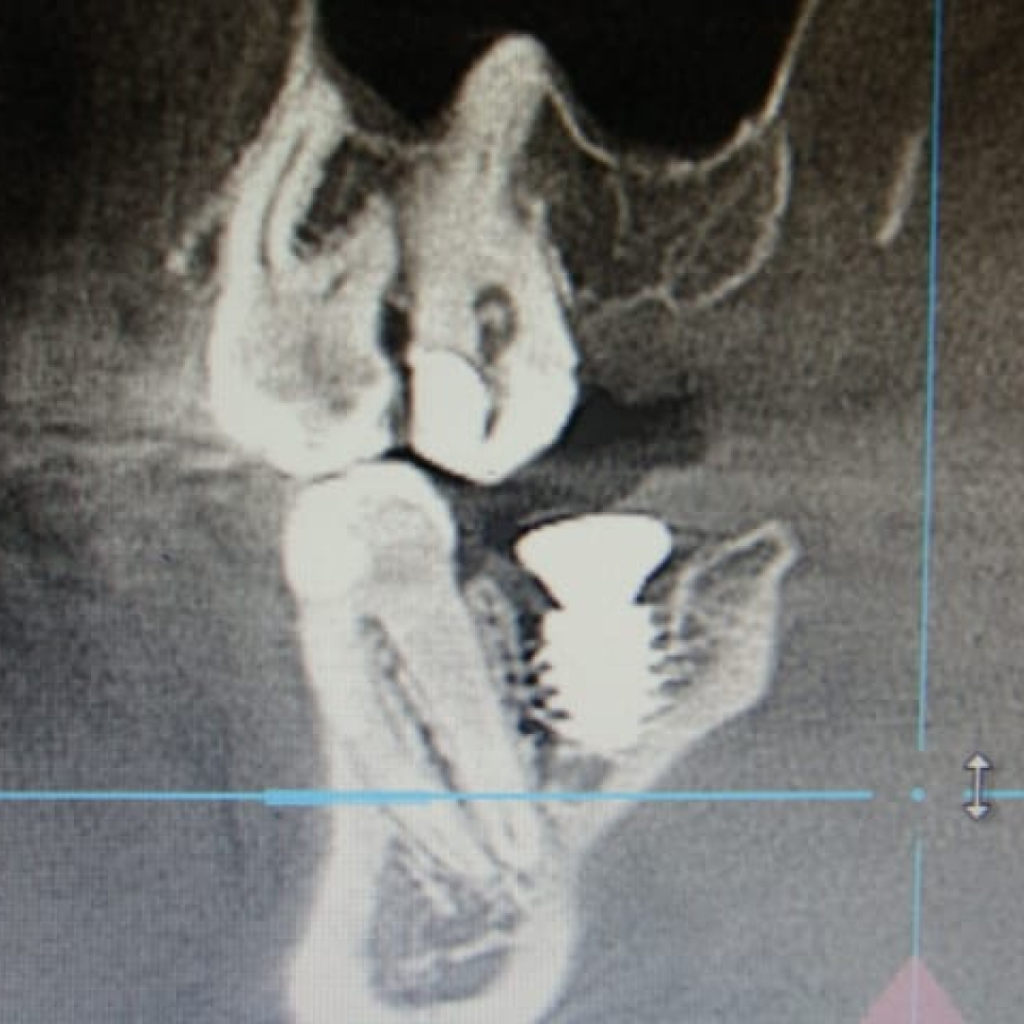

Этапы лечения. Зуб 37:

- Атравматичное удаление зуба

- Установка имплантата AnyRidge (Ø 8,0 мм, h 10,0), с торком 50-55 (данные ISQ 62-66)

- Установка формирователя десны Ø 8,0 мм

Этапы лечения. Зуб 47: